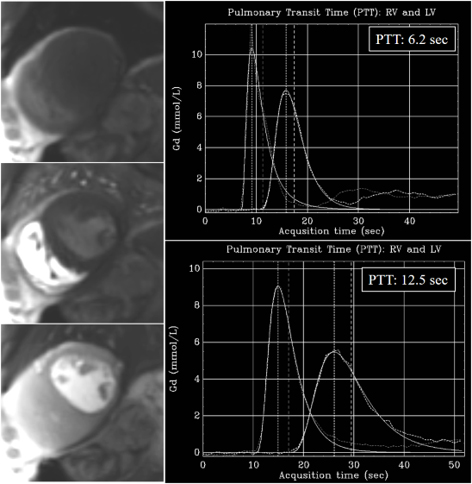

Although unrelated with MBF, an additional parameter of interest that is

automatically estimated in-line with the dual-sequence QP is the time interval

for the contrast-bolus to pass from the right to the left circulation, or

pulmonary transit time (PTT) (Fig. 36). As a measure of global cardiopulmonary

function, PTT has shown to be independently associated with cardiovascular events

[91], with longer values (

Fig. 36.PTT estimation from QP sequence. Left panel: time frames from a dynamic rest perfusion sequence before the arrival of contrast to the heart (top), at the enhancement of the right ventricle (middle), and, subsequently, of the left one (bottom). Right panels: gadolinium time-concentration curves from which PTT is automatically calculated inline. Note the striking difference between values from a normal subject (6.2 sec) (top) and from a patient with advanced ischemic cardiomyopathy and ejection fraction of 21% (12.5 sec) (bottom).